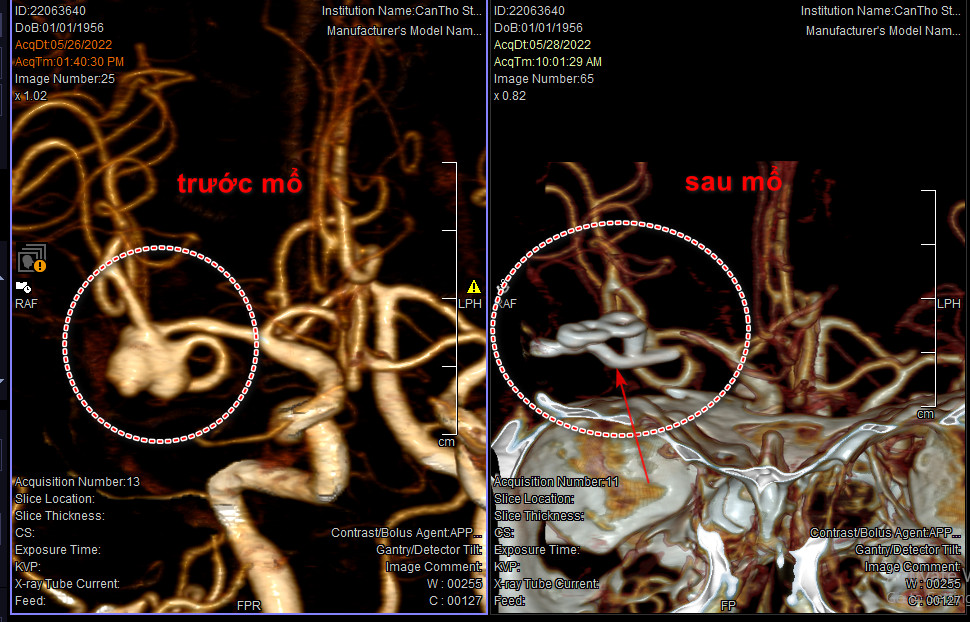

Đối với một túi phình có kích thước lớn, cổ rộng, máu chảy nhiều gây chèn ép não, khi can thiệp nội mạch DSA gặp khó khăn như trường hợp này, chúng tôi lựa chọn phẫu thuật kẹp cổ túi phình cầm máu, đồng thời lấy máu tụ đã chảy ra xung quanh túi phình, và điều quan trọng là phải bảo tồn được các mạch máu bình thường xung quanh…”.

Hình ảnh sau mổ cho thấy đã kẹp hoàn toàn cổ của túi phình, ngăn chặn dòng máu vào túi phình hiệu quả. (Ảnh: BVCC)

Hình ảnh sau mổ cho thấy đã kẹp hoàn toàn cổ của túi phình, ngăn chặn dòng máu vào túi phình hiệu quả. (Ảnh: BVCC)